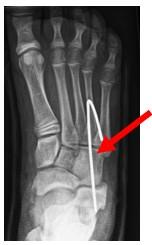

Plaatsen K draad in CC gewricht

Omdat het hielbot wordt verlengd komt het gewrichtje tussen de calcaneus (hielbot) en os cuboideum (teerling botje) onder spanning te staan. Om die reden wordt een ijzeren pinnetje (K draad) geplaats zodat dit gewrichtje niet uit de om gaat. Het draadje zal 6 weken blijven zitten en wordt tijdens een gipswissel op 6 weken na de operatie verwijderd.

Figuur 4: Röntgenfoto van de voet waarbij we zien dat de K draad (De witte lijn aan het einde vd pijl) in het CC gewrichtje is geplaatst.